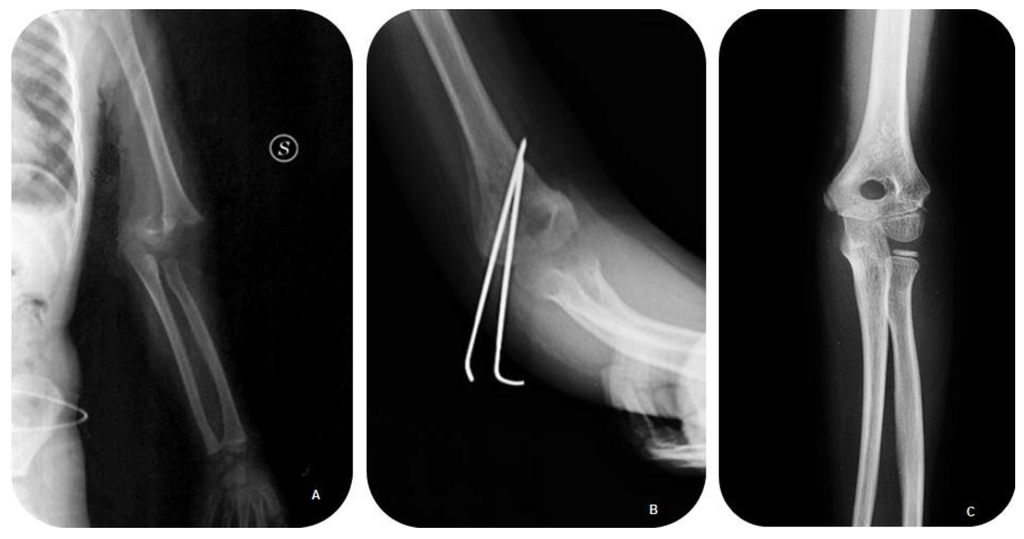

Surgical Treatment of Displaced Supracondylar Pediatric Humerus Fractures: Comparison of Two Pinning Techniques

2. Patients and Methods

3. Results